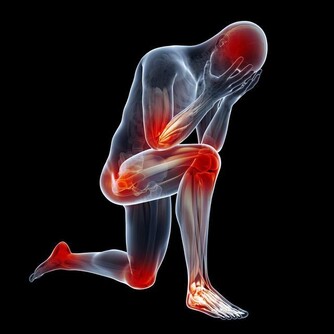

5、腿部經常抽筋

想要降低血脂,運動是必不可少,可以促進血液的循環,讓我們身體的血液流動更加快速,就有可能防止高血脂。